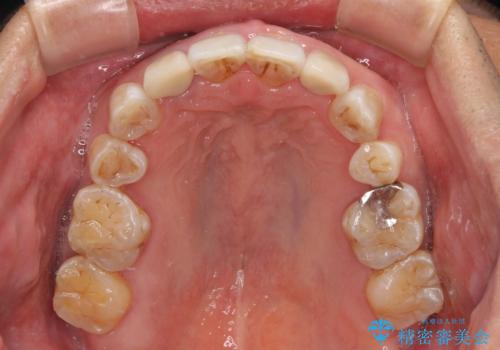

- 骨格的な咬み合わせのズレ、前歯のデコボコとクロスバイトを気にして来院された患者様です。

全額的にデコボコが強いため、上下左右の小臼歯計4歯を抜歯し、ワイヤー装置による矯正治療を行うこととしました。

抜歯する歯の一部をセオリーである第一小臼歯ではなく、第二小臼歯にすることで、骨格的なずれをカバーするように計画しました。

矮小歯であった上顎前歯2本は、矯正治療後にバランスの取れた大きさのオールセラミッククラウンを装着しました。